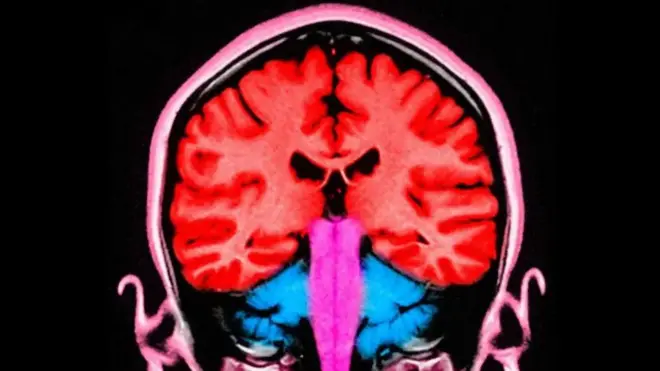

Авторы нового исследования «Как нейробиология объясняет синдром затяжного горя», опубликованного в журнале Trends in Neurosciences, сравнивали активность мозга при СЗГ с активностью, наблюдаемой при других психологических состояниях, и выяснили, что, несмотря на сходства, у людей с СЗГ значительно чаще наблюдаются более выраженные изменения в большем числе нейронных сетей, отвечающих за систему вознаграждения, которая в их случае зацикливается на умершем и не может найти вознаграждение где-либо еще.

Он рассказал, что участников исследования попросили вспомнить своих умерших близких или посмотреть на их фотографии во время процедуры сканирования мозга, чтобы выяснить, какие именно его части активизируются. В результате ученые обнаружили, что у людей с СЗГ значительно чаще наблюдаются изменения в нейронных сетях, отвечающих за систему вознаграждения.